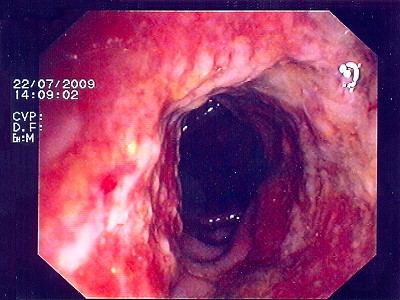

Abb. 4: Bei diesem bösartigen Gebilde handelt es sich um einen Krebstumor, der das Innere des Darmes nahezu vollständig verschlossen hat. Abb. 4: Bei diesem bösartigen Gebilde handelt es sich um einen Krebstumor, der das Innere des Darmes nahezu vollständig verschlossen hat.